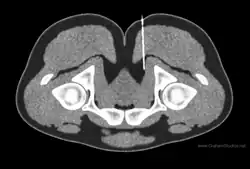

Diagnostic nerve blocks can confirm the clinical diagnosis for chronic pain as well as identify the entrapment site.[5] A diagnostic block is like an inverted palpation in the sense that palpation will cause a sensory nerve to send a signal (action potential) and a block will prevent a sensory nerve from sending a signal. By blocking nerve signals, the pain-contributing nerves can be identified or ruled out. Nerves are predisposed to entrapment in certain anatomical regions such as in an osteofibrous tunnels, through a muscle, adjacent to fibrous tissue.[6] Consequently, knowledge of these anatomical regions as well as peripheral nerve anatomy is an essential component to planning successful diagnostic blocks.[5] Ultrasound is a common form of image-guidance to place the needle properly, but it faces limitations visualizing small and deep nerves.[7] CT- or MRI- guidance are better positioned to access deep nerves as well as identify the anatomic level of the needle.[7]

MRI may be used to identify certain causes of entrapment such as a structural lesions pressing on a nearby nerve, but is prone to false negatives/positives and has poor correlation with the clinical examination.[8] A major limitation with MRI is that nerve tissue is resistant to imaging. An advancement of MRI that takes advantage of the tissue properties of nerves, called MR neurography (MRN), provides more detail. MR tractography (MRT) can also be of use in surgical planning as it can identify peripheral nerve abnormalities with a high correlation to intraoperative findings and has higher accuracy than MR neurography alone.[9] MRT uses diffusion tensor imaging to visualize the directional movement of water molecules along nerve tracts. Often an abnormality can be identified along tracts of nerve where water is not diffusing normally along the axis. MRT has been used to identify sacral nerve entrapment by the piriformis muscle, which would otherwise only be diagnosable with exploratory surgery.[10]